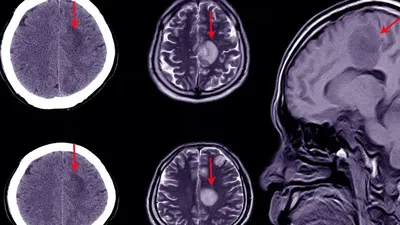

Embolizimi i arteries meningjeale të mesme (MMAE), një procedurë e re terapeutike, ka treguar se mund të parandalojë në mënyrë efektive rikthimin e hematomave subdurale kronike, pra gjakderdhjet në tru që shfaqen pas ndërhyrjeve kirurgjikale. Kjo qasje shoqërohet me rrezik më të ulët të dështimit të trajtimit krahasuar me terapitë standarde, pa rritur rrezikun e goditjes së rëndë në tru apo vdekshmërisë afatshkurtër.

Hematoma subdurale subakute dhe kronike janë të shpeshta, veçanërisht te personat e moshuar. Edhe pas heqjes kirurgjikale, e cila pritet të bëhet procedura neurokirurgjikale kraniale më e shpeshtë deri në vitin 2030, sëmundja rikthehet te 8–20% e pacientëve.

Pse ndodh rikthimi i gjakderdhjes?

Edhe pas heqjes kirurgjikale, këto hematoma shpesh “sillen sikur kanë një rrjedhë të tyre”, shpjegon dr. Jason Davies, docent i neurokirurgjisë dhe informatikës biomjekësore nëUniversity at Buffalo (SUNY) dhe hulumtues kryesor i studimit EMBOLISE.

“Gjatë disa javëve, teksa mpiksja shpërbëhet, formohen membrana që furnizohen me gjak nga dura mater. Këto membrana janë të prirura për rrjedhje dhe gjakderdhje të re, edhe pas drenazhit. Hipoteza bazë e MMAE është se mund t’i ‘thajmë’ këto membrana duke mbyllur arterien që i furnizon me gjak, duke parandaluar kështu rikthimin.”